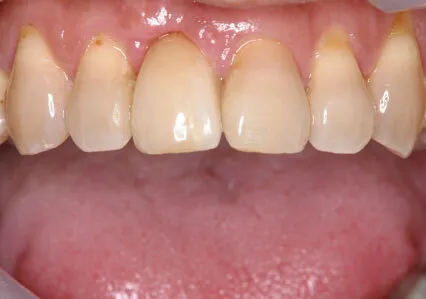

症例③

| 主訴 | 他院にて抜歯後、歯を入れたい |

|---|---|

| 診断名 | 歯根破折 |

| 年齢 | 46歳 |

治療に用いた装置(治療法) | 骨造成・インプラント |

| 部位 | 右上1 |

| 治療期間 | 8か月 |

| 治療費用 | 造成:55,000円 インプラント:462,000円 |

| リスク・副作用(治療に関する) | 腫服、しびれ |